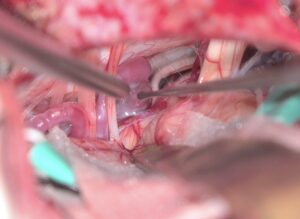

87歳女性、繰り返しブロックを行いガンマナイフも行った、難治生三叉神経痛を手術しました。高齢ですが無事一発治癒しました。 2025 12/11 顔面痙攣・三叉神経痛 2025年12月11日87歳でできるだけ手術を避ける方針で、投薬、ブロック、ガンマナイフを行ってきましたが、とうとう手術になりました。幸い合併症や脳梗塞が生じることなく治癒しました。最初から手術すべきと言う人もいますが、私は、やはり本人の納得が一番大切だと思います。ScreenshotScreenshot 顔面痙攣・三叉神経痛 よかったらシェアしてね! URLをコピーしました! URLをコピーしました! 251013月 休日なので小浜、大飯町、美浜へ温泉&ドライブ 251016木 高嶋浩央先生が入局を決心してくれました この記事を書いた人 kikuta 関連記事 2603月 67歳男性の右顔面痙攣を手術しました。 2026年3月22日 2603月 58歳女性の左顔面痙攣を治療しました。VAとAICAの複合型圧迫でしたがうまく治癒できました。 2026年3月21日 46歳男性、開眼できないほどのVA型左顔面痙攣を手術しました。術後まだ完全には消失していませんが痙攣は著明に軽減しました。 2026年3月3日 19歳女性の三叉神経痛を手術しました。術後痛みは消失した様子です。 2026年3月3日 左三叉神経痛の手術をしました。カルバマゼピンで抑えられい強い痛みがありましたが、手術後痛みが完全になくなり食事も取れるようになりました。 2025年12月5日 2025年8月 78歳 VA型の顔面痙攣の神経減圧術を行いました。M-TEPを併用し無事治癒しました 2025年12月4日 2025年5月 テグレトールで治らない左三叉神経痛の手術を行い直後より痛みは消失しました。 2025年9月25日 畑山式MVDハンズオンセミナーに東野先生と参加してきました 2025年3月22日